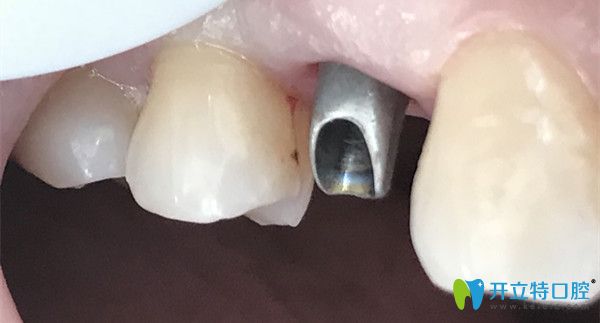

種植牙馬上就要鑲好了

牙齒帶好牙冠的照片